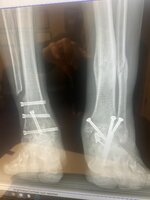

I've got issues with my ankles as you can see. I bought some Kenetrek EverStep Orthopedic boots. They have made a huge difference for me. You might want to check them out.

• Ankles.jpg